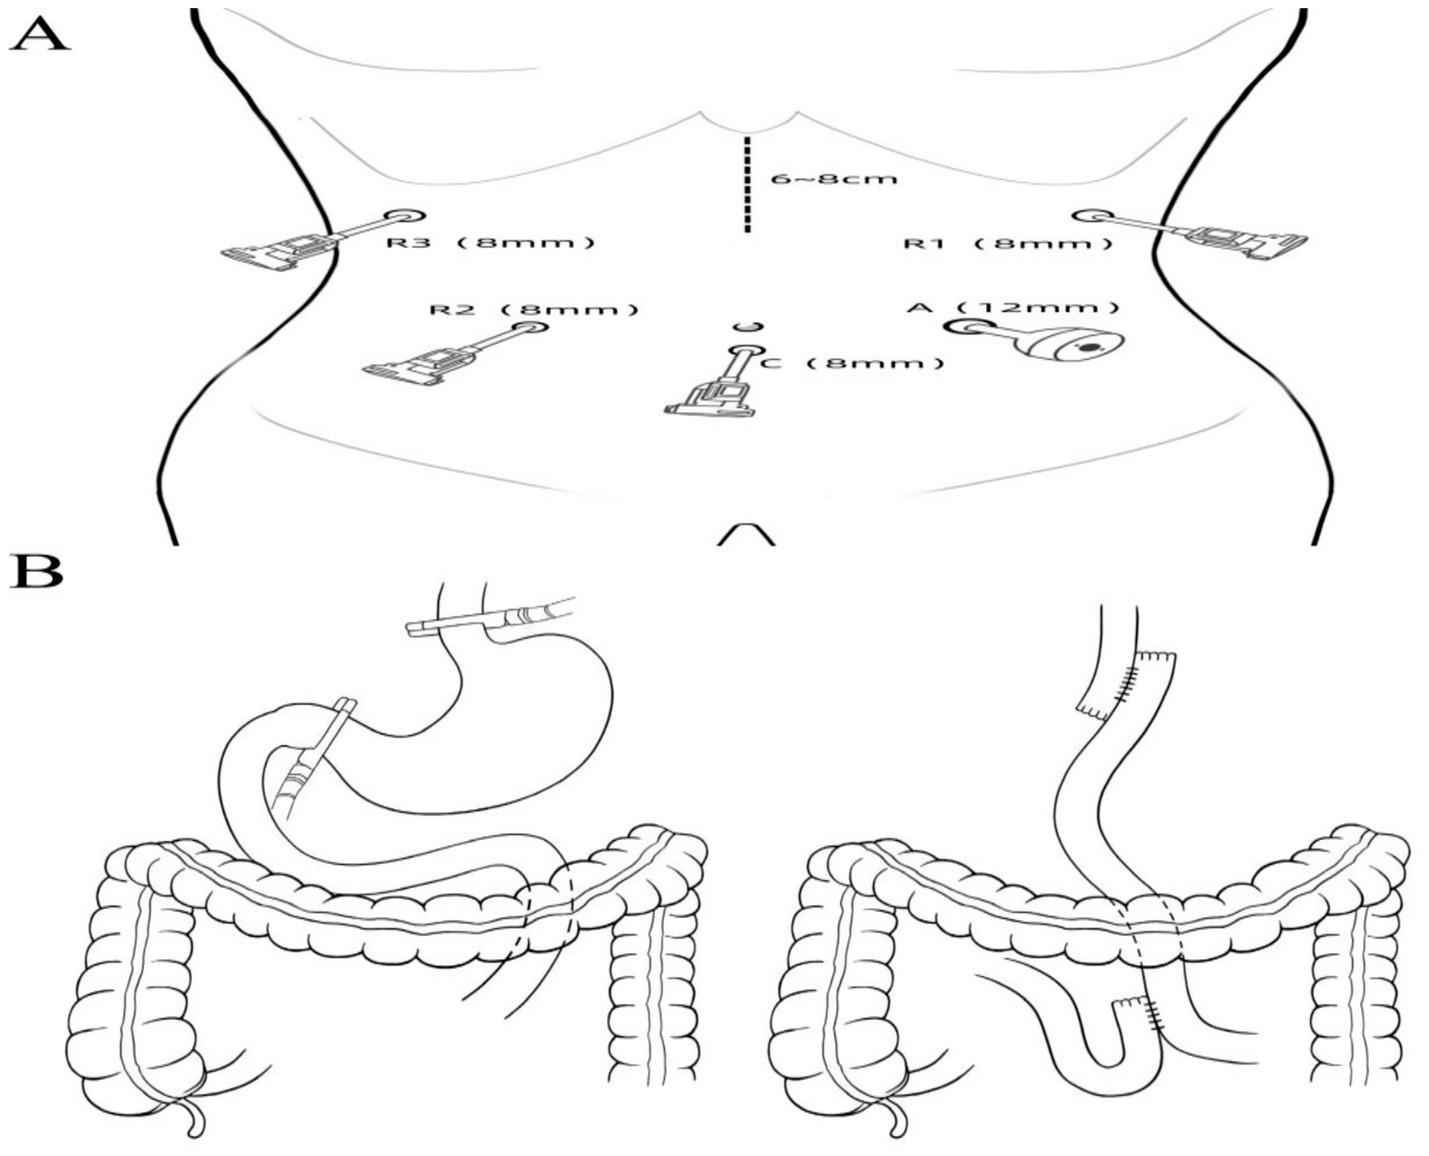

1. After successful general anesthesia, a gastric tube, urinary catheter, and central venous catheter were placed. The patient was positioned supine with legs apart, and standard sterile draping was performed. A 1 cm infraumbilical incision was made for pneumoperitoneum with CO2 insufflation maintained at 12 mmHg. A trocar was inserted as the camera port (C, 8 mm). The patient was placed in a 15° Trendelenburg position. Exploration assessed the diaphragm, liver, paracolic gutters, pelvis, small intestine, peritoneum, omentum, and mesentery. Findings included diffuse gastric wall thickening and edema, firm texture, significant gastric enlargement, multiple soft perigastric lymph nodes (~5 mm), extensive adhesions, marked perigastric vascular proliferation, and mild pelvic effusion. Robotic-assisted total gastrectomy was deemed feasible. Additional ports were placed: R1 (8 mm, left anterior axillary line, subcostal), for harmonic scalpel; R2 (8 mm, right midclavicular line, umbilical level), for Maryland bipolar forceps; R3 (8 mm, right anterior axillary line, subcostal), for Cadiere forceps; and A (12 mm, left midclavicular line, umbilical level), as an assistant port. The “arc-shaped five-port” configuration was used (Figure 2A). The liver was suspended to fully expose the subphrenic cardia and esophagus.

3. A 6–8 cm upper midline incision was made below the xiphoid, with layered entry into the abdomen and placement of a wound protector for specimen retrieval. The jejunum was transected approximately 25 cm distal to the ligament of Treitz using a 60 mm laparoscopic linear stapler (white cartridge, 2.6 mm staple height). The distal jejunum was brought up retrocolically to the esophageal stump without tension. A 0.5 cm mesenteric-side enterotomy was made and dilated at the jejunal limb, 40 cm from the distal end, and at the proximal and distal stumps. Side-to-side jejunojejunostomy was performed with a 60 mm linear stapler (white cartridge, 2.6 mm), and the common enterotomy and stump were closed with 3–0 absorbable knotless sutures, reinforcing the duodenal stump. Mesenteric defects were closed. After re-establishing pneumoperitoneum, an esophagojejunostomy (overlap technique) was performed at the distal jejunal stump, with closure and reinforcement using 3–0 absorbable knotless sutures. Resection and anastomosis diagrams are shown in Figure 2B.

Figure 2. (A) Trocar placement for surgical access. (B) Schematic illustration of the extent of surgical resection and digestive tract reconstruction.